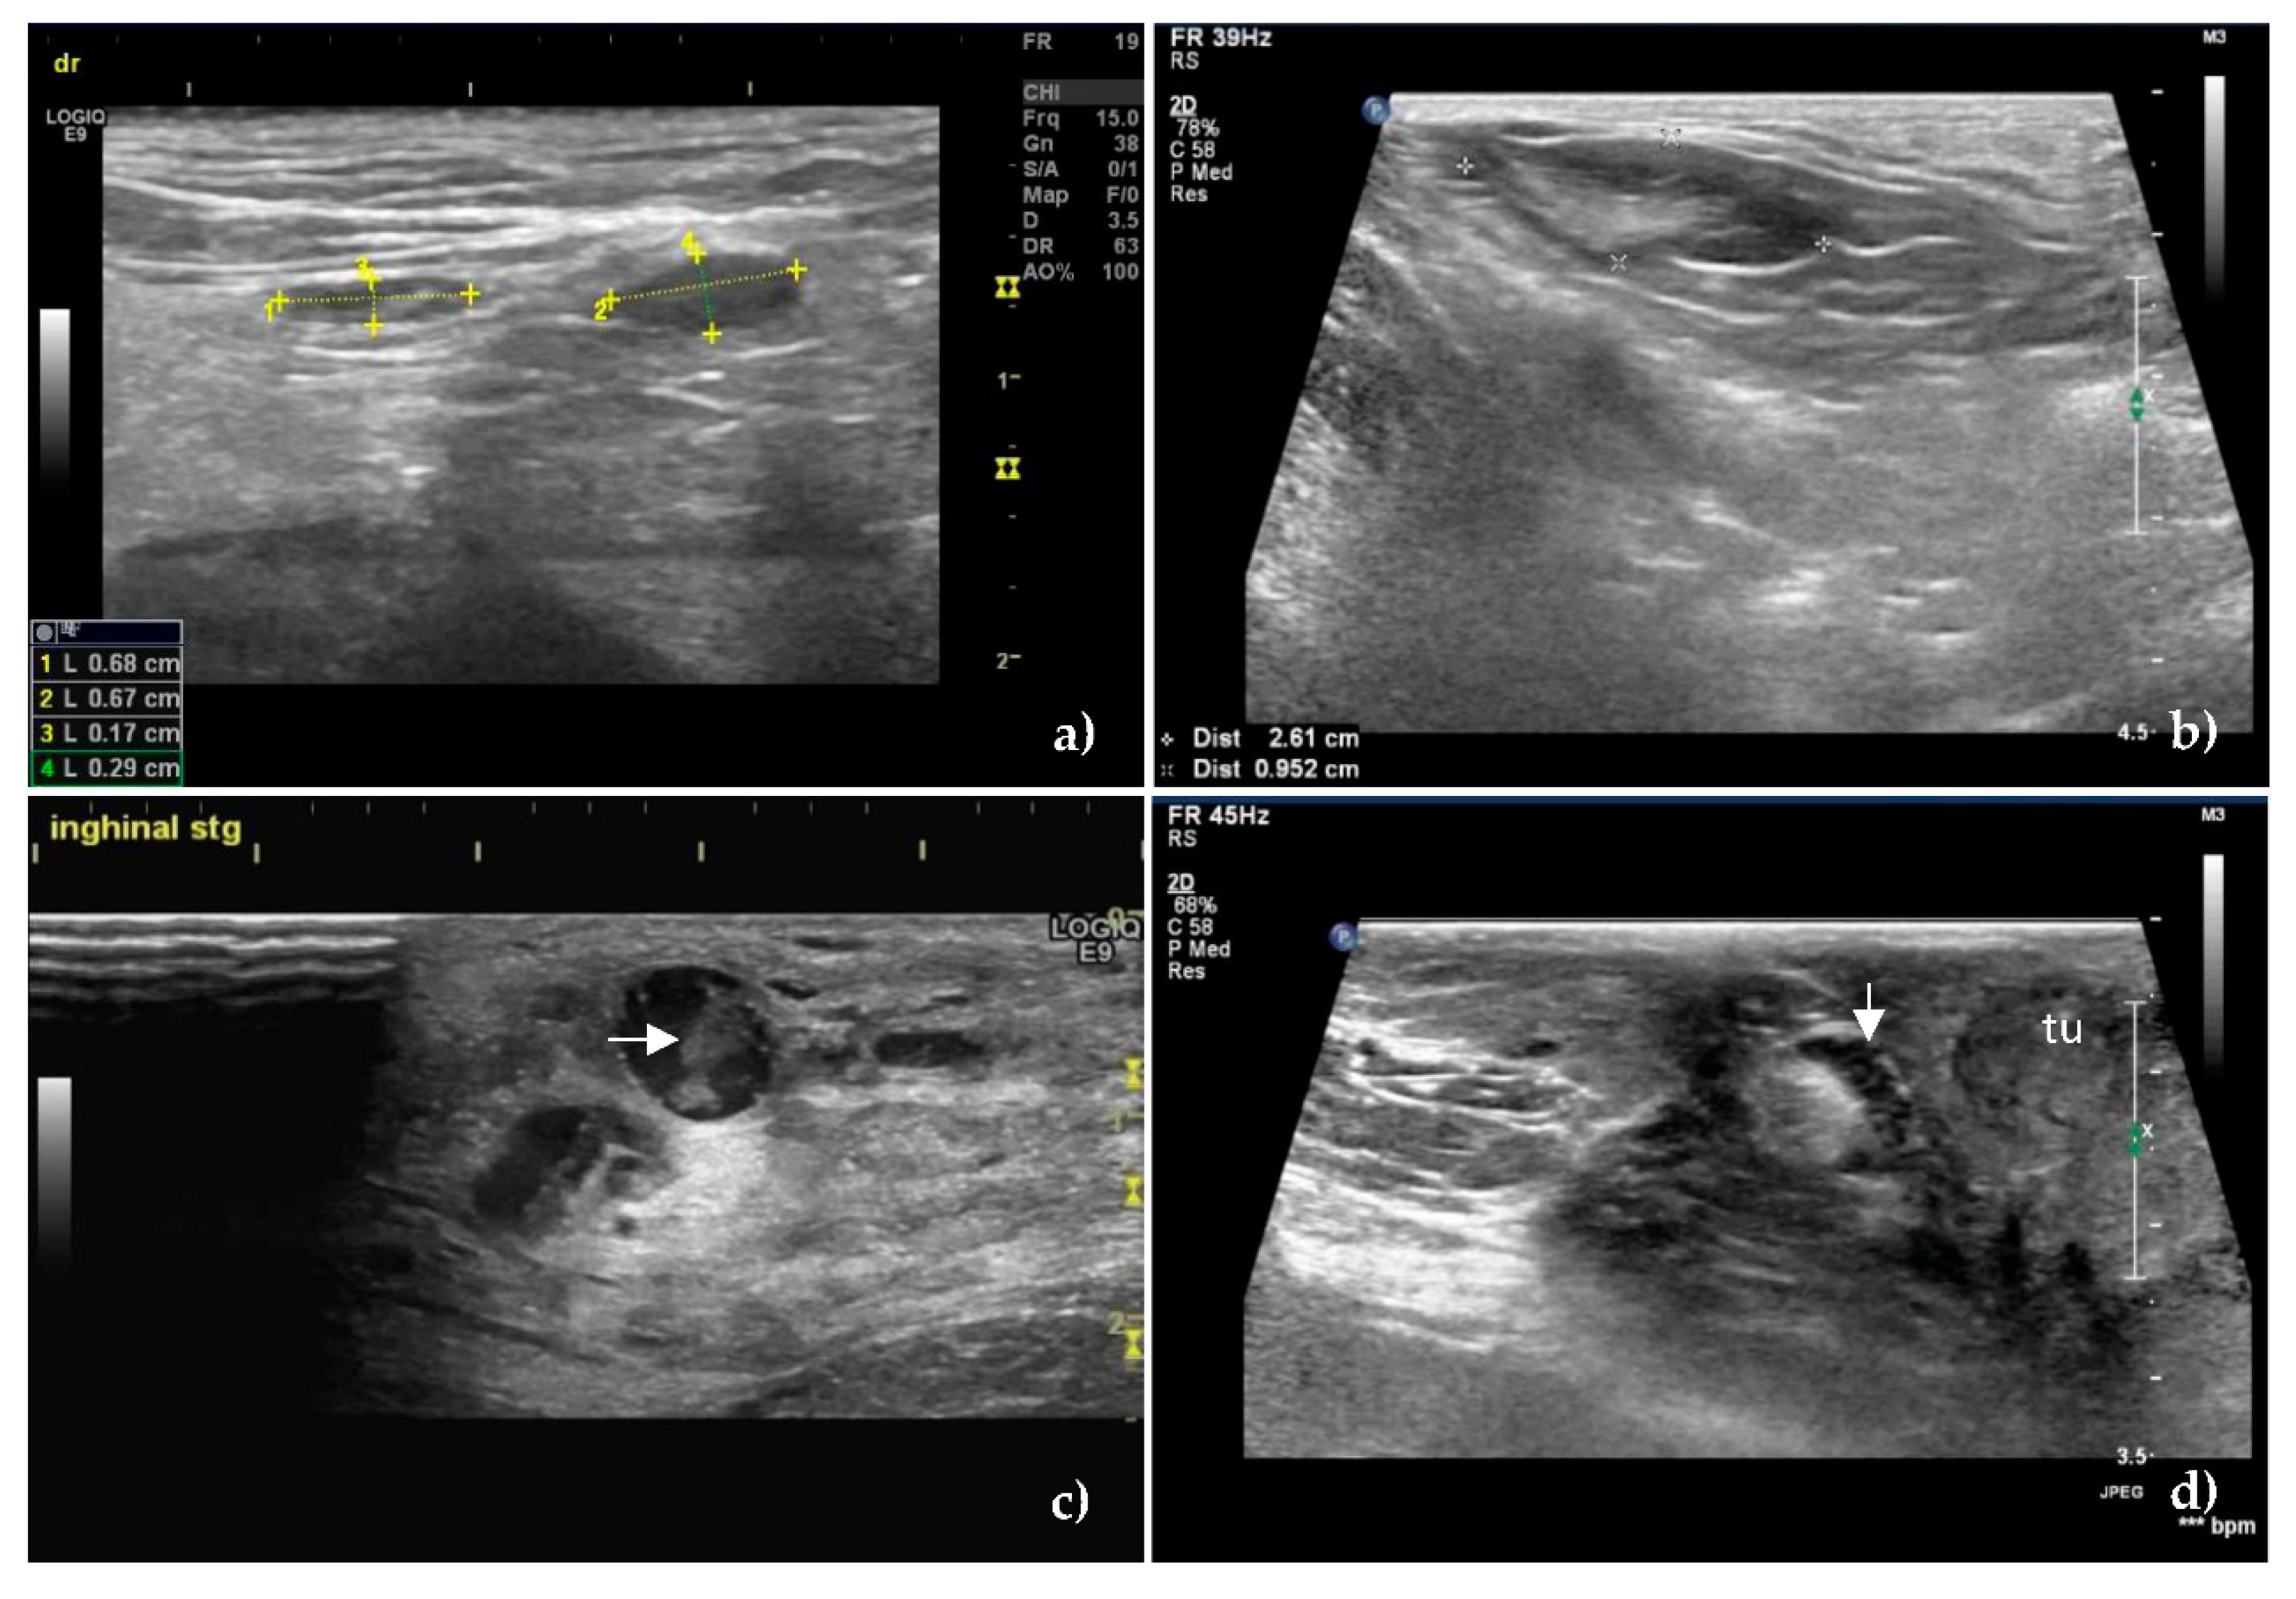

At greyscale US, the S/L axis ratio value >0.55 was the most significant predictive sign for the presence of metastases in the SLNs (Figure 1), having a sensitivity of 83.3% and a specificity of 78.6%.

Figure 1. B-mode ultrasound images of unaffected (a,b) and metastatic, (c,d) sentinel lymph nodes. Oval shape, S/L ratio less than 0.5, homogeneous echostructure and hyperechoic hilum of unaffected superficial inguinal sentinel lymph nodes in (a) and axillary sentinel lymph node in (b). The numbers in the image and the lower left corner of Figure 1a represent the long axis (1 and 2) and short axis (3 and 4) measurements of the examined SLNs. The distance between the two “+”signs in Figure 1b represents the measurement of the long axis, and the distance between the two “×” signs represents the measurement of the short axis of SLN. The values are found in the lower left corner of Figure 1b. (c) Metastatic superficial inguinal sentinel lymph node showing rounded shape, hypoechoic pattern, and inhomogeneous echostructure with coagulation necrosis inside of lymph node (horizontal arrow) as an echogenic structure which leaves no shadows. (d) Cortical thickening of a metastatic superficial inguinal sentinel lymph node (down arrow) located near a tumor—tu.

The mean S/L ratio was lower in the unaffected SLNs (0.50 ± 0.09), compared to the metastatic ones (0.65 ± 0.13) with p < 0.001. The same characteristic was maintained in terms of the mean value of the short axis—0.67 ± 0.26 in unaffected SLNs, versus 1.17 ± 0.53 in metastatic SLNs, respectively 1.33 ± 0.46 mean value of the long axis in unaffected SLNs versus 1.83 ± 0.79 in metastatic SLNs.

The homogeneity in the unaffected SLNs was obvious (Figure 1a,b), compared to the inhomogeneous metastatic lymph nodes, (p < 0.001) (Figure 1c,d). There was no statistically significant difference between the echogenicity of the two categories of SLNs. The majority of the unaffected SLNs were hypoechoic (66.6%) or isoechoic (23.8%), features which were found in the metastatic SLNs too, rated as hypoechoic (68.51%) or isoechoic (25.92%), p = 0.81. The hyperechoic pattern was found in 9.52% of the unaffected SLNs and 5.55% of the metastatic SLNs.